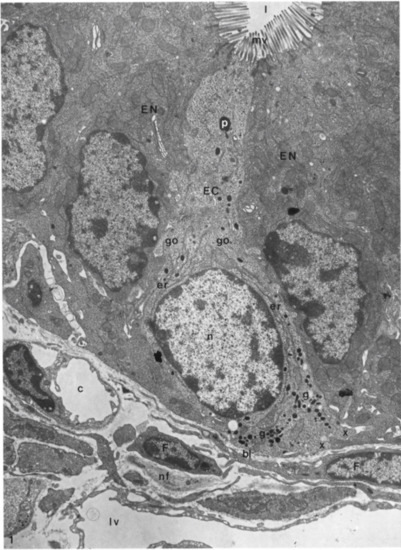

Figure 8. Longitudinal section of an enterochromaffin cell from the basal lamina to the lumen of a duodenal crypt, in which it is possible to recognize a fenestrated capillary, fibroblast, lymph vessel, and nerve fibers. Moreover, it is also possible to highlight the presence of rough endoplasmic reticulum, secretory granules, Golgi complexes, microvilli, phagosome, and basal cytoplasmic extensions of the enterochromaffin cell. EC: enterochromaffin cell; bl: basal lamina; l: lumen; c: capillary; nf: nerve fibers; lv: lymph vessel; F: fibroblasts; EN: enterocytes granules; g: secretory granules; go: Golgi complexes; mv: microvilli; p: phagosome; x: basal cytoplasmic extension. X 9.600. The Figure is obtained from Wade et al., (1985). Reprinted by permission from Springer Nature Customer Service Centre GmbH: Springer Nature, Cell and Tissue Research (License Number 5232430326152, 19 January 2022) [33].

The evaluation of EECs has been reviewed extensively by light- and electron-microscopical techniques [31,32,33,34]. All these findings showed that these cells are identifiable by their secretory granules, as reported above. These granules are present in cytoplasmic vesicles; they have a characteristic size and shape for each cell type [35]. Based on these evaluations, it is now widely accepted that ECs are also classified according to their secretory products [32,33,36]. Thus, they were distinguished from other EECs by their pleiomorphic, electron-dense secretory granules [33,37]. Furthermore, Wade and Westfall (1985) showed that ECs extended from the basal lamina of the crypt epithelium to the lumen of the crypt in the duodenum of mice [33] (Figure 8).

As can be seen in Figure 8, ECs showed a tuft of microvilli extending into the lumen of the GI tract, rough endoplasmic reticulum in the perinuclear region, secretory granules concentrated near the nucleus and at the base of the same cell. These granules were different in size and showed oblong, spherical, and biconcave shapes (Figure 9).

A very important finding was that ECs have bundles of nerve fibers below the epithelium basal lamina together with many fenestrated vessels. These considerations suggested that there were synaptic relationships between neuronal fibers and ECs even if, at the time, they had not been confirmed or previously reported in other studies [33].

The presence of vessels in proximity to ECs has supported the idea that their secretory products have endocrine functions. Their products were transported by the blood stream to their site of action and finally, when a cell secretes a product, it normally causes a local or paracrine function with potent effects on intestinal tissues [33].

These authors did not find granules/secretory products in the apical cellular region. On the contrary, other researchers identified an evident bipolarity of ECs with the presence of secretion products not only in the basal but also in the apical portion of the same cells [34,38]. The presence of granules in the apical portion showed an apical exocrine release of their products; this concept has been supported by the presence of Golgi apparatus in the apical cytoplasm with many microtubules that provide a pathway for the transfer of newly formed secretory products from these organelles to the liminal surface of the ECs. Instead, many of these granules in the basal portion of ECs suggested their endocrine function.